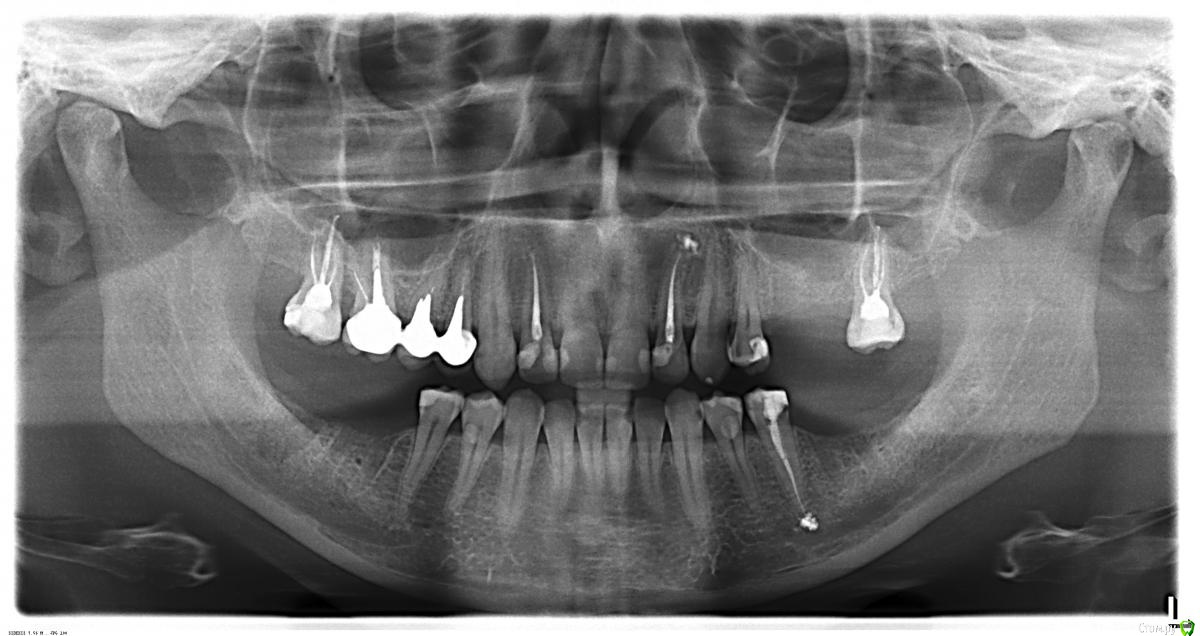

AlexanderGudkov Опубликовано 21 июня, 2015 Поделиться Опубликовано 21 июня, 2015 (изменено) Я бы предложил такой план (вкрадце):- диагностика/перелечивание каналов зубов 17,16,15,14,27,34- коронки на эти зубы- имплантаты в позиции 25,26,36,37,46,47- коронки на имплантаты Изменено 21 июня, 2015 пользователем AlexanderGudkov Ссылка на комментарий

Гарриевич Опубликовано 21 июня, 2015 Поделиться Опубликовано 21 июня, 2015 (изменено) А 16,15,14 - что там не в порядке?корневые каналы зубов пролечены плохопо снимку как будто полупустыедля более точной диагностики нужны прецельные снимки всех леченных зубов в остальном: идеальнее замещать дефекты имплантатами2 импланта снизу слева, два снизу справа и два наверху слева естественно для точного планирования имплантации нужна КТ ПС никаких круговых мостов Изменено 21 июня, 2015 пользователем Гарриевич Ссылка на комментарий

Большой Зеленый Опубликовано 21 июня, 2015 Поделиться Опубликовано 21 июня, 2015 Скорее всего нужен будет синуслифтинг слева вверху . Ссылка на комментарий